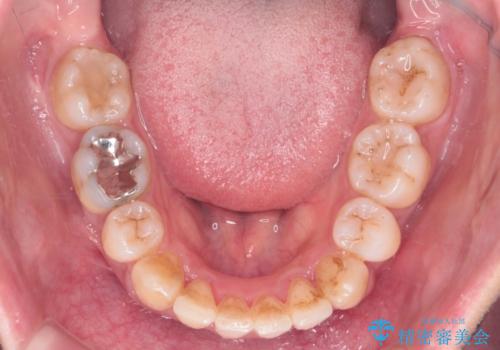

矯正治療で歯並びを治した後、乳歯を抜いたところにブリッジを入れています。

左上の奥歯はすれ違っていたためそのかみ合わせも整えています。

歯を抜いて治療を行ったため、Eラインが整った形で治療ができました。口が断然閉じやすくなっています。